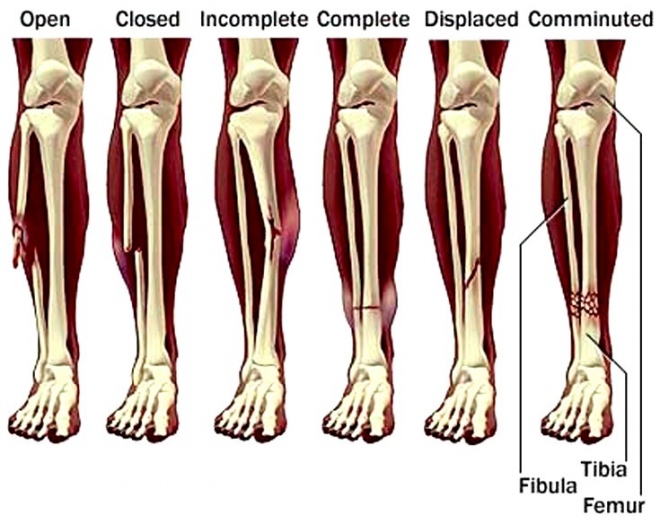

Τα κατάγματα της κνήμης διαιρούνται σε δύο είδη:

α) τα οφειλόμενα σε βαρεία κάκωση (π.χ. τροχαία) οπότε είναι και συντριπτικά και

β) τα οφειλόμενα σε στροφική κάκωση, τα ονομαζόμενα σπειροειδή.